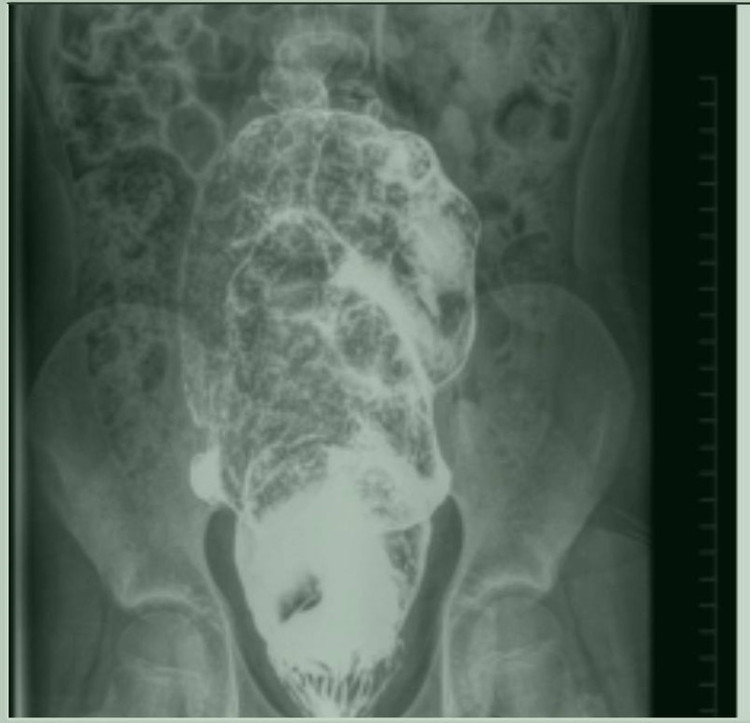

Sau khi nhập viện tại Bệnh viện Nhi đồng 2, bé V. được thăm khám khám, chụp X-quang đại tràng có cản quang, sinh thiết hút trực tràng. Kết quả sinh thiết em mắc bệnh Hirschsprung (phình đại tràng) đoạn ngắn. Phần trực tràng sát hậu môn không có tế bào hạch thần kinh là nguyên nhân gây ra bệnh táo bón kéo dài.

| Phần ruột bệnh nhi lúc nào cũng ứ đọng phân trong khung đại tràng - Ảnh BVCC |